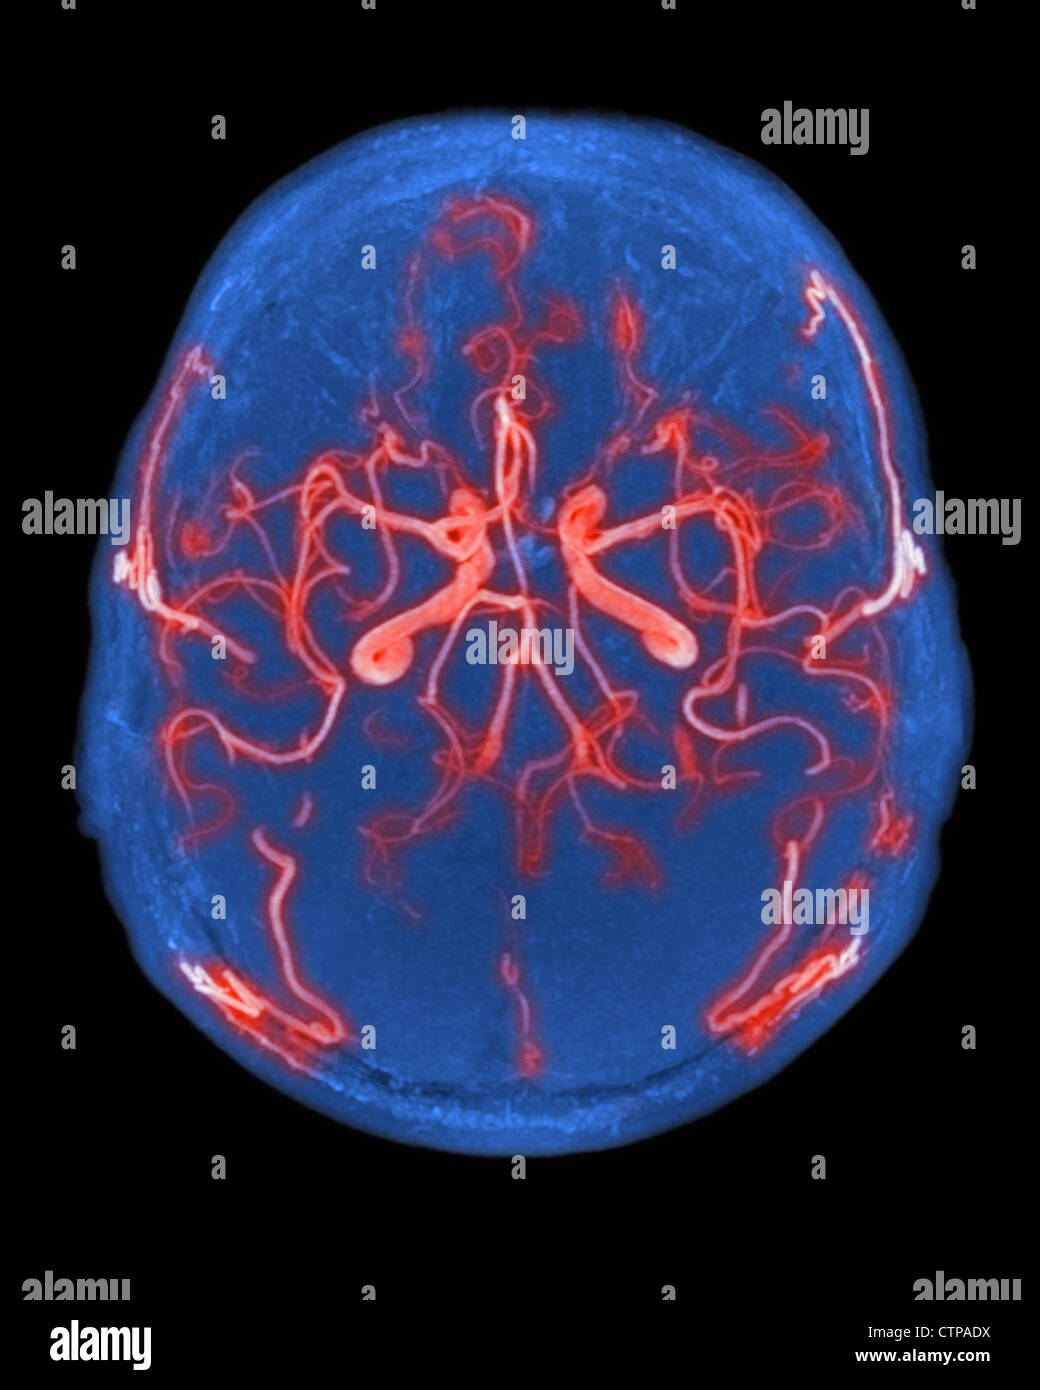

RMJE9NWM–Dieses anatomische Bild zeigt die Arterien unter dem Gehirn, einem wichtigen Teil des menschlichen Kreislaufsystems. Die Arterien sind dafür verantwortlich, das Gehirn mit Blut zu versorgen und seine Funktion zu gewährleisten. Die Nahansicht hilft beim Verständnis ihrer Struktur und Rolle für die Gesundheit und Funktion des Gehirns.